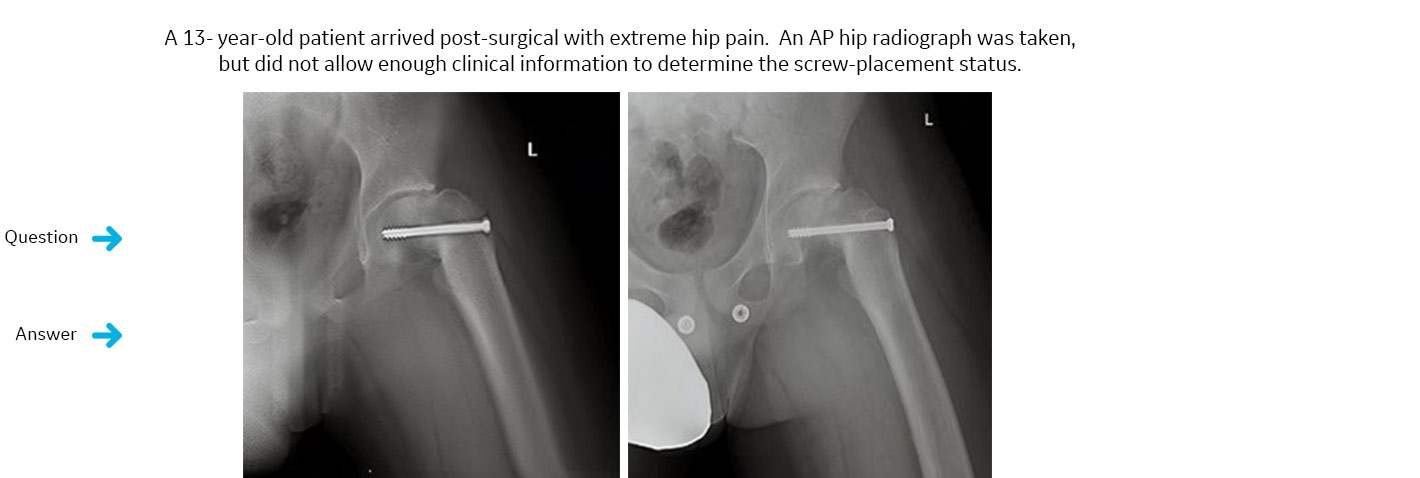

Il mezzo di sintesi impiantato ha invaso lo spazio articolare?

La radiografica di controllo dell’anca in esame nella sola proiezione AP non consente di determinare il corretto posizionamento del mezzo di sintesi.Risposta diagnostica risolutiva: no

La radiografica di controllo dell’anca in esame nella sola proiezione AP non consente di determinare il corretto posizionamento del mezzo di sintesi. Si effettua acquisizione “volumetrica” in VolumeRad che consente la rimozione delle strutture anatomiche sovra- e sottostanti, consentendo una diagnosi accurata e precisa. In effetti, la singola fetta (slice) in VolumeRad ha rivelato che il mezzo di sintesi impiantato non ha invaso lo spazio articolare. Comunque il paziente è stato sottoposto ad un secondo intervento chirurgico che ha confermato il corretto posizionamento dell’impianto.